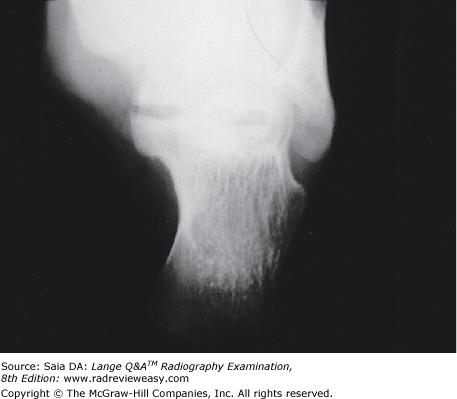

The radiograph shown in Figure 2–15 demonstrates the articulation between the

- talus and the calcaneus

- calcaneus and the cuboid

- talus and the navicular

2 and 3 only